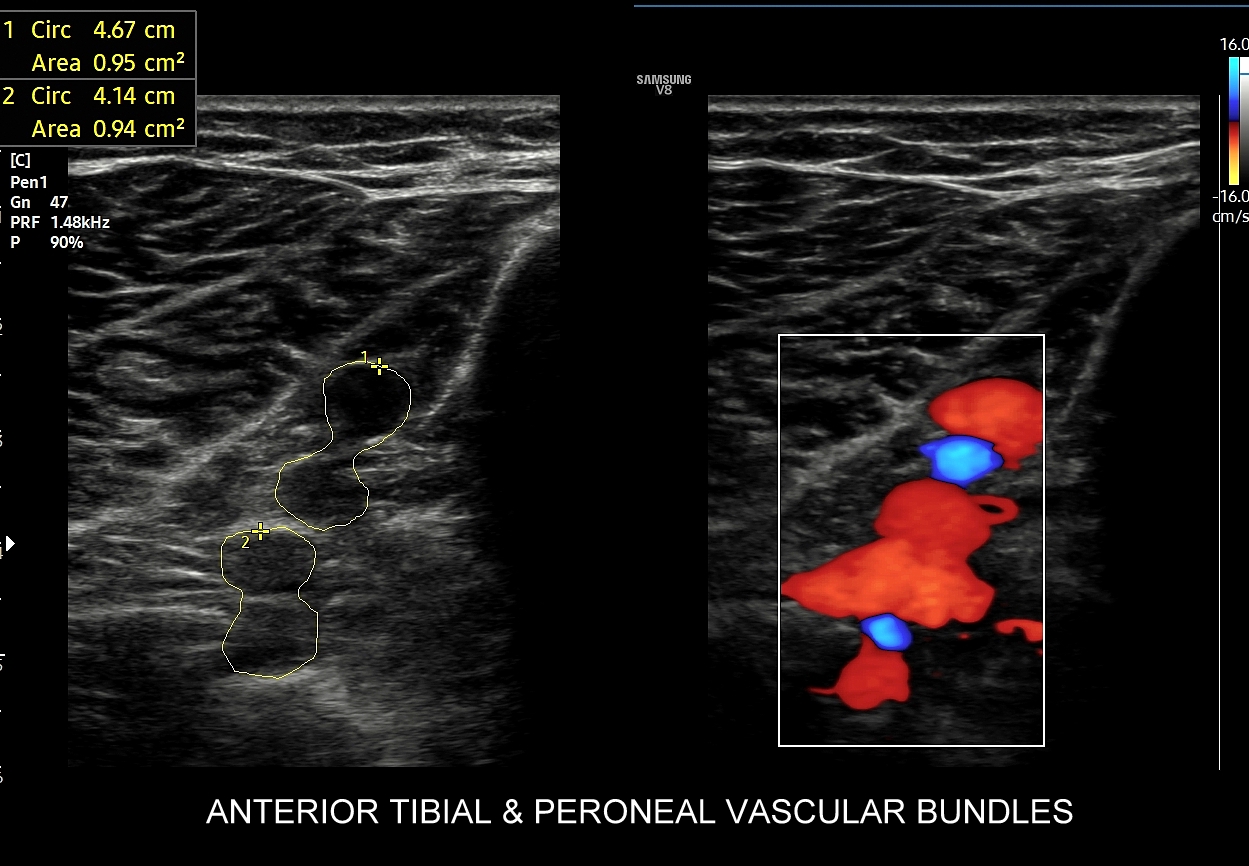

- Z kolei profile o wysokiej pulsacyjności charakteryzują się tym, iż posiadają wąskie i ostre piki skurczowe, a w fazie rozkurczowej odwrócone lub/i nieobecne przepływy. Profile tego typu występują w tętnicach unaczyniających kończyny.

W przypadku tętnic podążających do kończyn w warunkach spoczynkowych obserwuje się charakterystyczne wielozałamkowe profile przepływów zawierające od 2 do nawet 4 następujących po sobie przeciwstawnych załamków o zmniejszającej się amplitudzie, przy czym w tętnicach tych zwykle nie obserwuje się ciągłego przepływu w fazie rozkurczowej. Stały lub prawie stały przepływ rozkurczowy, tj. przepływ o pośredniej pulsacyjności, może pojawić się w tętnicach kończyn w trakcie intensywnego wysiłku fizycznego.